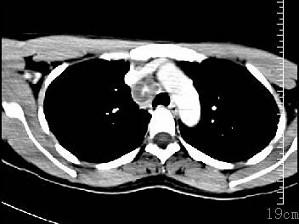

问题 女性35岁,发热、盗汗近3个月,颈部摸到多个结节,CT扫描如图所示,请选择最可能的诊断 ( )

选项 A、淋巴结核 B、淋巴瘤 C、结节病 D、淋巴转移癌 E、神经鞘瘤

答案 A